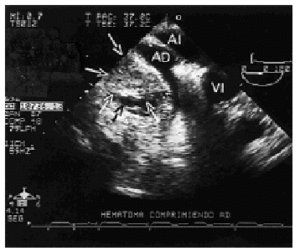

Se orientó como taponamiento pericárdico y la ecocardiografía transtorácica mostró un derrame pericárdico ligero que no explicaba el cuadro clínico, por lo que se realizó un ecocardiograma transesofágico, que documentó una compresión extrínseca de la aurícula derecha con colapso total de la cavidad por un hematoma retroauricular (fig. 1). En la misma unidad de cuidados intensivos se reabrió en la zona subxifoideo un punto del final de la herida quirúrgica de la esternotomía, suficiente para introducir una cánula quirúrgica de aspiración. Guiándose mediante control ecocardiográfico se logró aspirar el coágulo (fig. 2). La paciente recuperó la estabilidad hemodinámica, la diuresis y el volumen minuto a los pocos minutos de liberar la compresión extrínseca de la aurícula derecha.

Figura 1. Imagen inicial obtenida por ecocardiograma transesofágico, en la que se aprecia compresión con colapso de la aurícula derecha por compresión por el hematoma pericárdico. AI: aurícula izquierda; AD: aurícula derecha; VI: ventrículo izquierdo; hematoma delimitado por flechas.